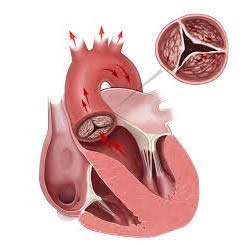

Стеноз

Клапанные створки срастаются, что приводит к уменьшению диаметра отверстия. Это затрудняет отток крови из желудочка.

Недостаточность

Створки не могут полностью закрываться из-за повреждений, что позволяет крови из аорты возвращаться в желудочек.

Сложность замены аортального клапана

Протезирование аортального клапана сердца выполняется на открытом сердце. После того как грудная клетка вскрыта, орган подключается к аппарату искусственного кровообращения. В случаях, когда пациент находится в критическом состоянии или наблюдается нестабильная гемодинамика, операция может быть проведена без полного раскрытия.

Методы данного хирургического вмешательства предполагают доступ к сердцу через бедренную вену. Весь процесс контролируется с помощью специального экрана, на который выводится изображение сосудов с использованием контрастных веществ.

Этапы операции

После предварительной подготовки, описанной ранее, и введения общей анестезии, хирургическая операция включает в себя следующие этапы:

- обработка операционного поля;

- продольное рассечение грудины и вскрытие полости перикарда;

- подключение аппарата искусственного кровообращения;

- выполнение манипуляций на сердце (удаление поврежденного клапана);

- установка искусственного протеза;

- контроль работы вживленного протеза и проверка швов;

- отключение аппарата искусственного кровообращения и «запуск» сердца;

- наложение швов.

Процедура осуществляется под общим наркозом. Обработка миокарда на протяжении всей операции (не менее 2 часов) осуществляется с использованием холодного физраствора.